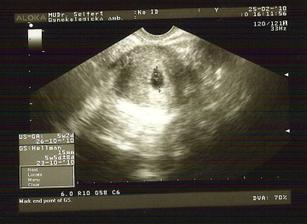

25.2.2010 kontrola dopadlo skvěla kulíšek je tam kde má být a je 14mm velký, tedy ne miminko, ale celý gestační váček